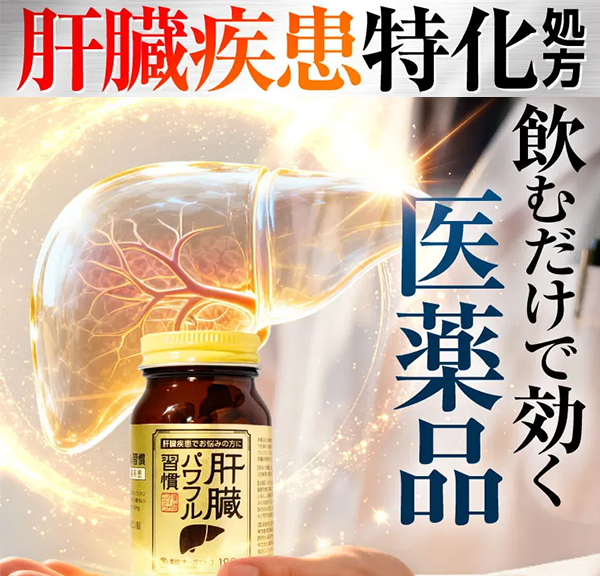

肝臓パワフル

肝臓ケアを考えた、W成分設計

肝臓パワフルは、グルクロノラクトンとタウリンを同時に配合◎

他にも肝臓の作用に関わる有効成分が、合わせて6つも含まれていて “解毒・排出・代謝” をサポートしてくれる!!

だから、飲むだけで肝臓疾患に効くんです!

さらに、肝臓パワフルは創業100年以上の製薬会社によって製造されている医薬品です。

GMP認定工場で厳格な品質管理のもと製造されているため、信頼性も◎